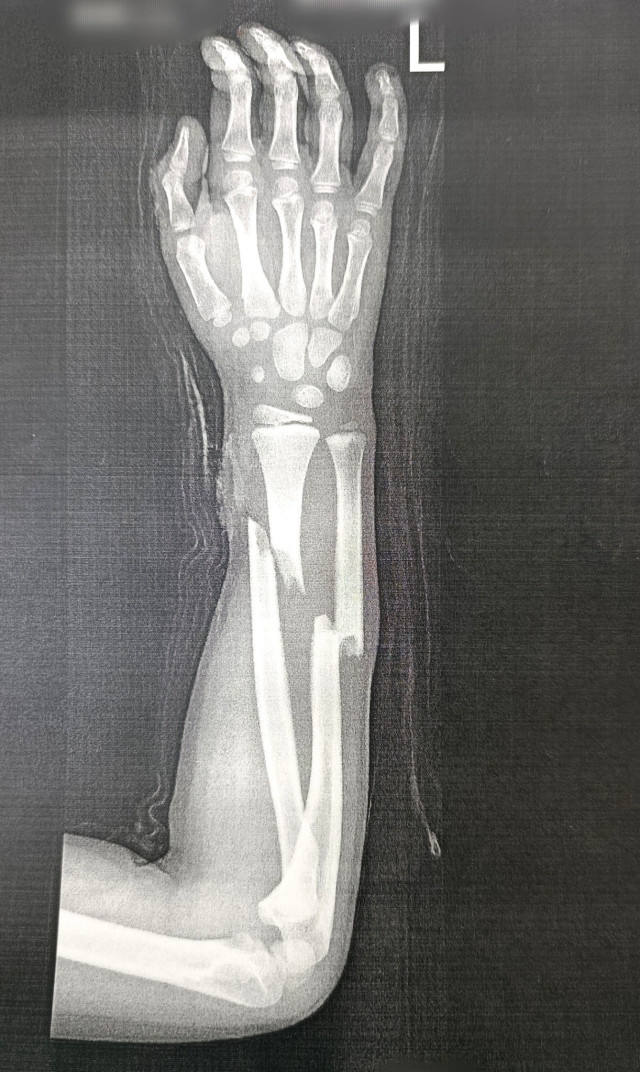

У відділення екстреної медичної допомоги Володимирського ТМО госпіталізували дитину з відкритим переломом ліктьової та променевої кісток. Причина травми – невдалий стрибок на батуті.

Досвідчені ортопед-травматологи медзакладу, працюючи злагоджено та професійно, провели екстрену успішну операцію сучасним малоінвазивним методом – металоосинтез (МОС ТЕN). Цей метод вважається одним із найкращих в травматології та ортопедії.

Для максимальної безпеки та комфорту маленького пацієнта лікарі-анестезіологи застосували провідникову анестезію, що дозволило ефективно знеболити руку, мінімізуючи навантаження на організм.

Втручання пройшло без ускладнень, стан дитини стабільний.